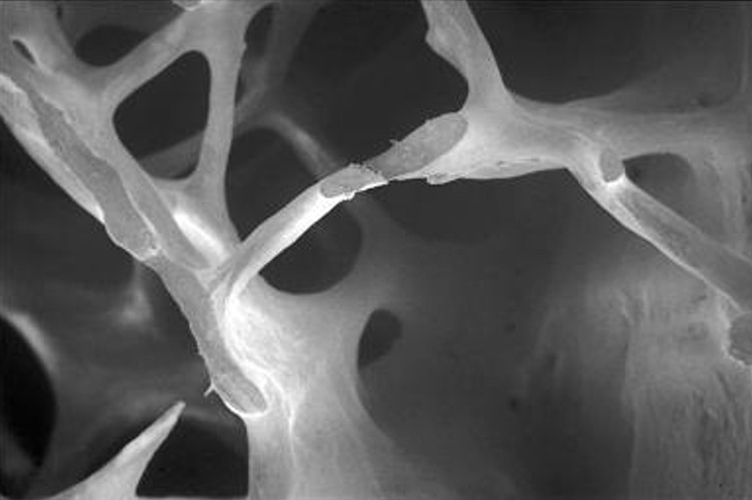

Osteoporosis is a systemic skeletal disease that causes a reduction in bone mass and microarchitectural deterioration, leading to fragile bones and an increased risk of fractures. As bones become weaker, even minor impacts or falls can result in significant injuries, making it essential to understand the causes and management options available.

The bone remodeling cycle can be separated into two distinct processes: (i) bone resorption, where cells called osteoclasts function in the resorption of mineralized tissue and (ii) bone formation, where cells called osteoblasts are responsible for bone matrix synthesis and subsequent mineralization of the bone. In healthy individuals, bone resorption is matched by new bone formation.

Osteoporosis develops as the balance between bone resorption by osteoclasts and bone formation by osteoblasts is not maintained, and not enough bone tissue is formed, leading to frail and fracture-prone bones.